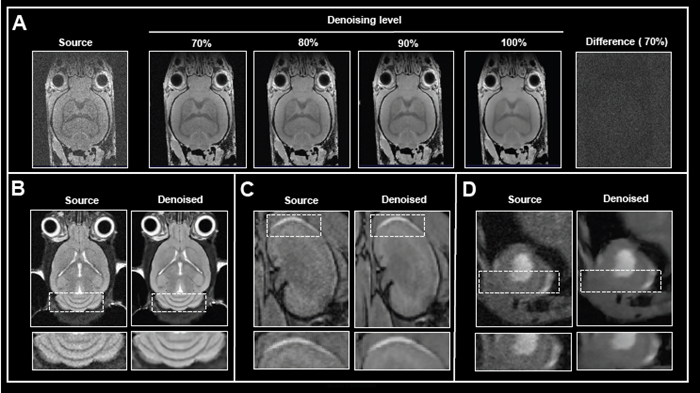

In addition to network options, the denoising level can be selected. Fig 2A shows the effect of applying various levels of denoising to image reconstruction.

Mouse brain data was obtained ex vivo, and the original data was rebuilt without and with increasing denoising levels (70-100%). Increasing the level of denoising produces images with gradually less noise. Importantly, no artifacts were introduced during the procedure.

Computing the difference images between the source and 70% denoised images revealed that only noise was selectively eliminated. If the original signal at the image's edges is reduced due to bandwidth selection, high denoising levels (90 and 100%) can result in a hazy look of edges.

The appropriate denoising level, which balances efficient noise removal with edge blurring, must be determined for each data set or, at the very least, each application protocol.

Figure 2. The effect of image denoising on image quality. A) Applying increasing levels of denoising. Shown are axial images of a 3D T1-weighted FLASH ex vivo data of a fixed mouse head acquired at 9.4 Tesla without (Source) and different levels (70-100 %) of denoising. A difference image between the source and 70 % denoised images was computed. B)-D) Comparison of in vivo images reconstructed with no denoising and with 70 % denoising. B) Coronal T2-weighted TurboRARE images of a mouse brain acquired at 3 Tesla. C) Coronal 3D FISP images of mouse kidney acquired at 7 Tesla. D) Short axis view of a mouse heart acquired with a flow-compensated triggered FLASH sequence at 9.4 Tesla. For different data, either no denoising (Source) or denoising using individual networks and a pre-denoising of 50 % was applied (Denoised). Image Credit: Bruker BioSpin Group

The efficacy of Smart Noise Reduction was illustrated using in vivo mouse data from various organs collected at various magnetic field strengths (Fig 2B-D).

Compared to reference images of the brain, kidney, and heart, reconstruction with 70% denoising resulted in images with substantially less noise and a better look of anatomical details and edges.